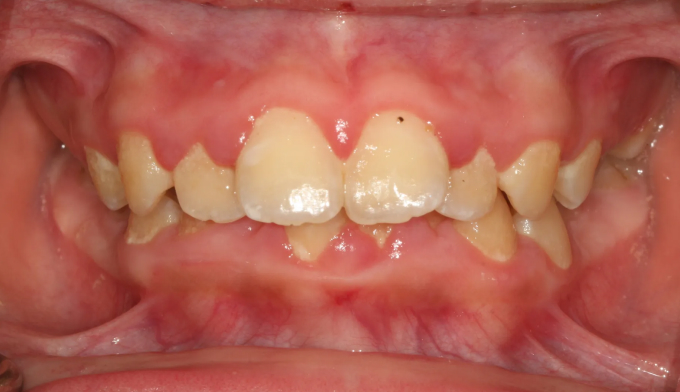

덧니,

돌출입

10대

2025.02.11